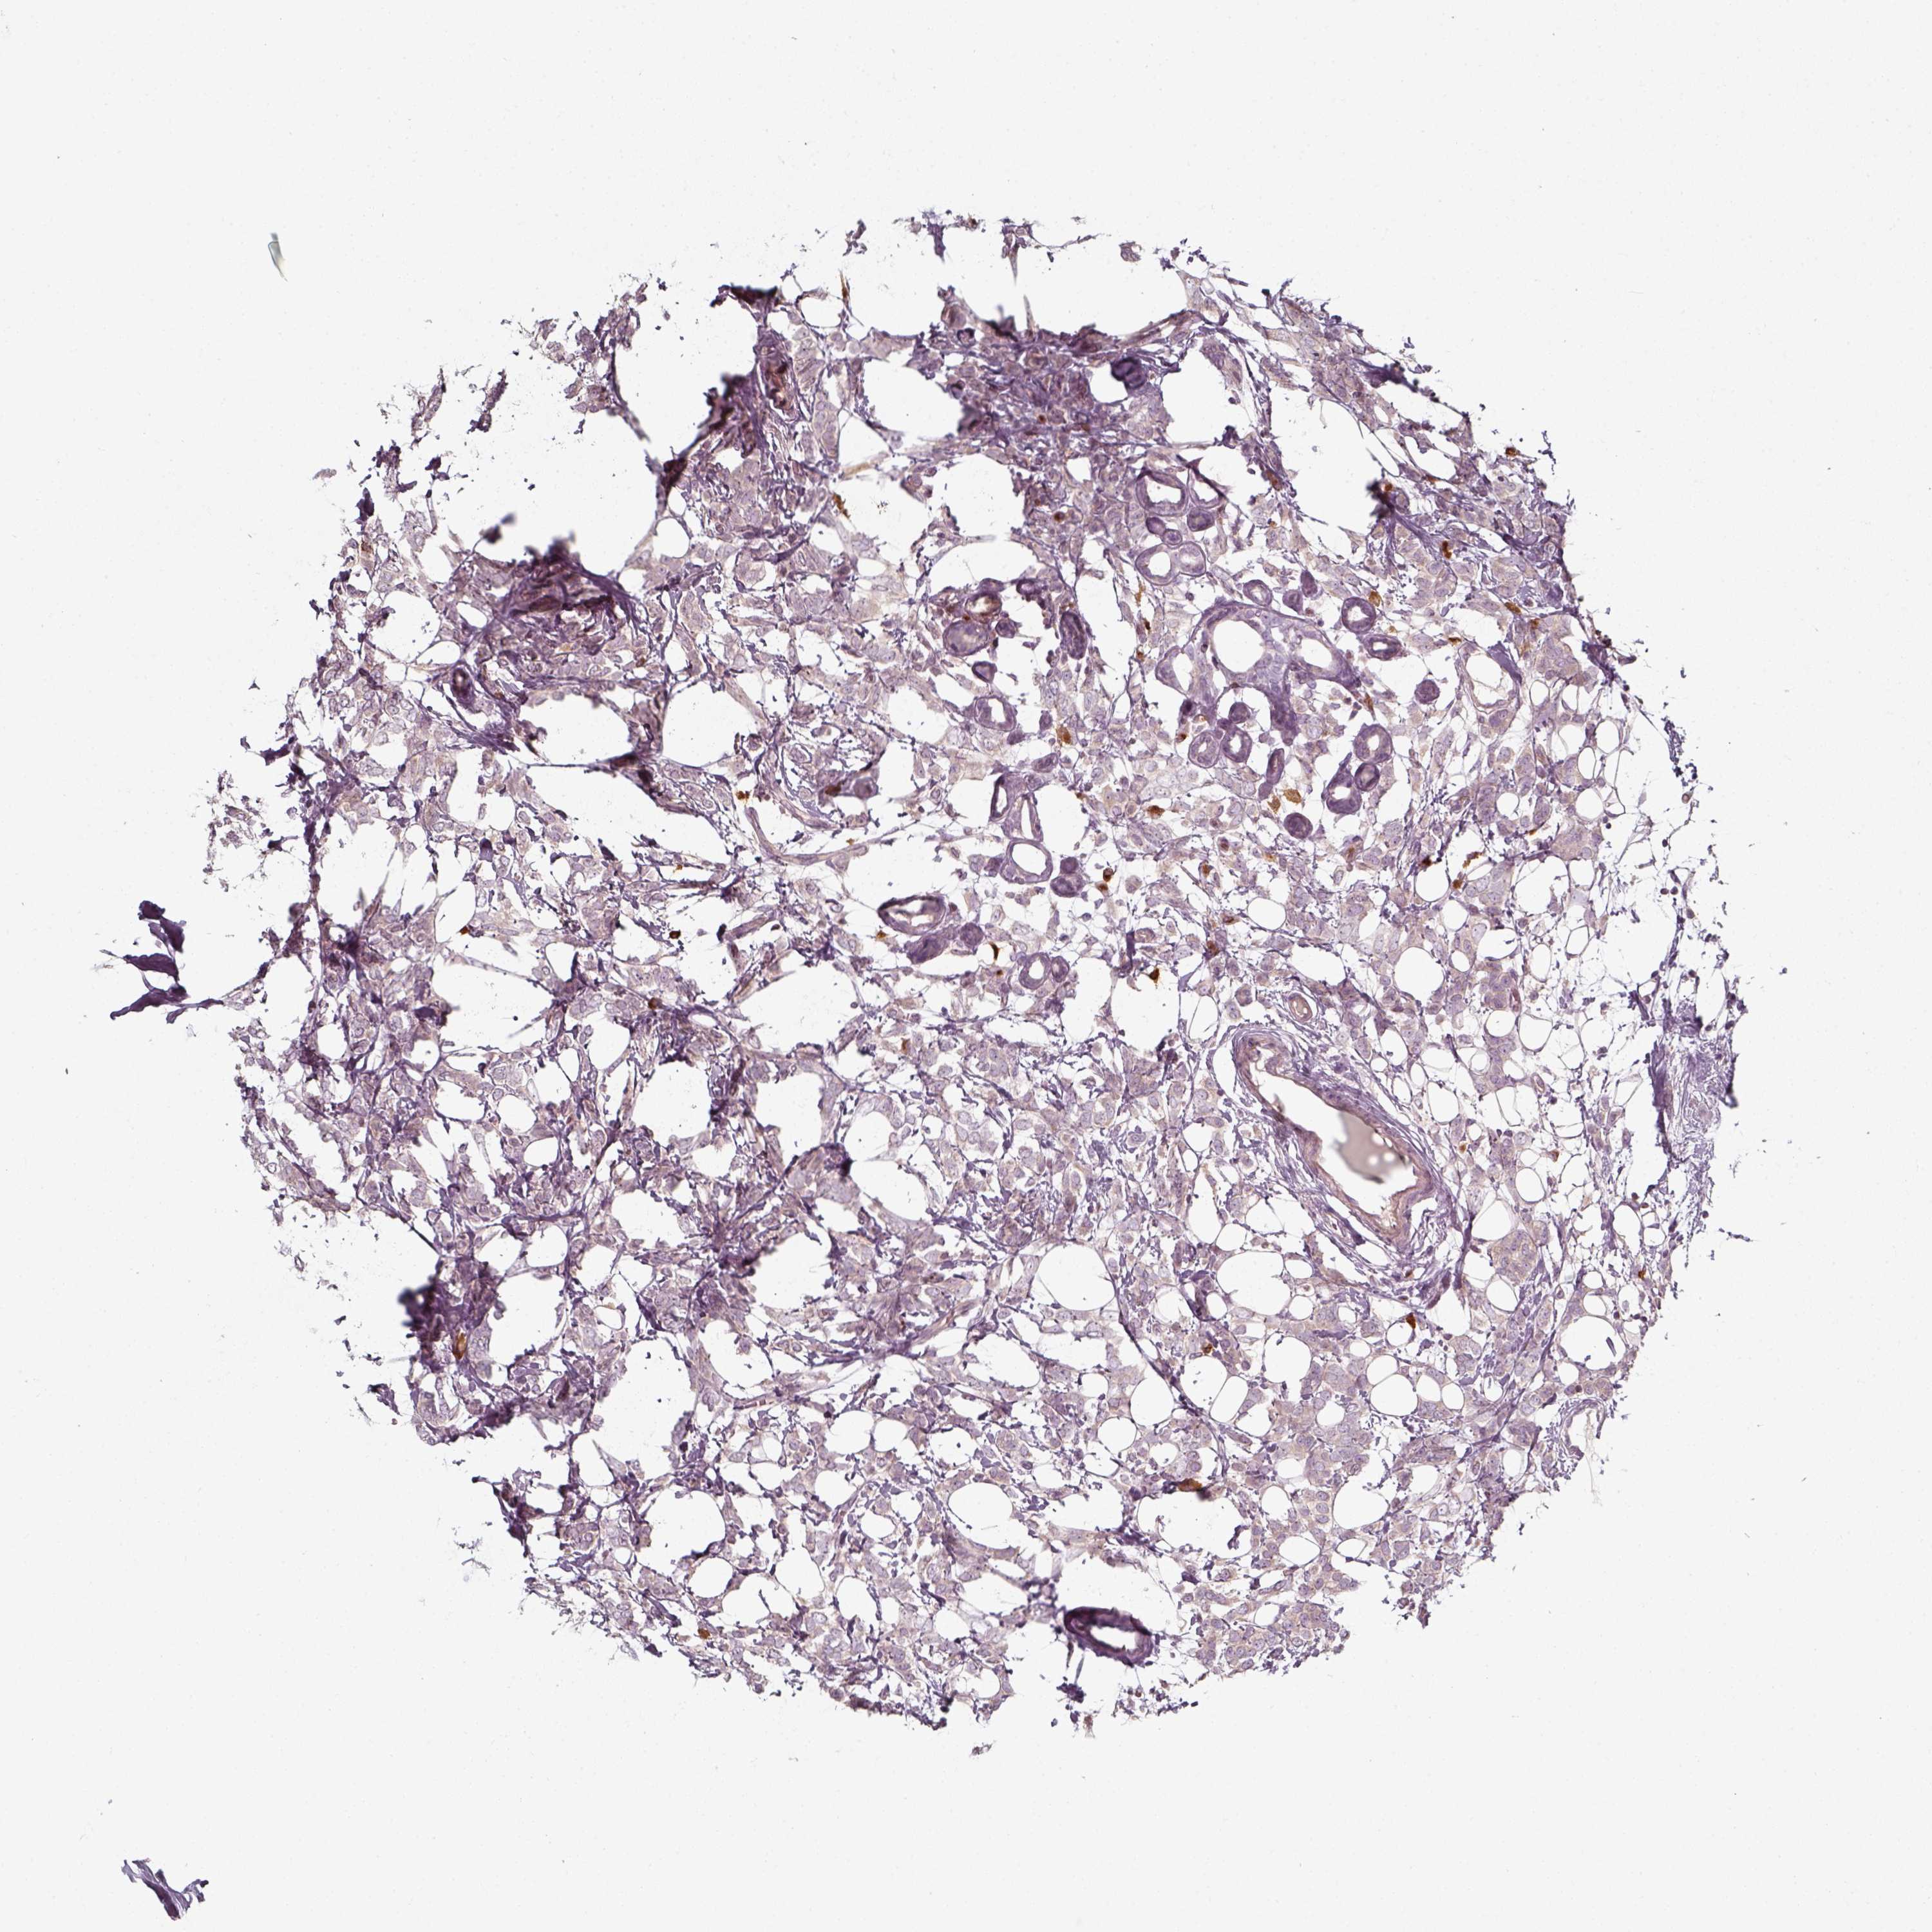

CANCER BREAST CANCER Show tissue menu

BRCA TCGA BRCA VALIDATION PROTEIN EXPRESSION